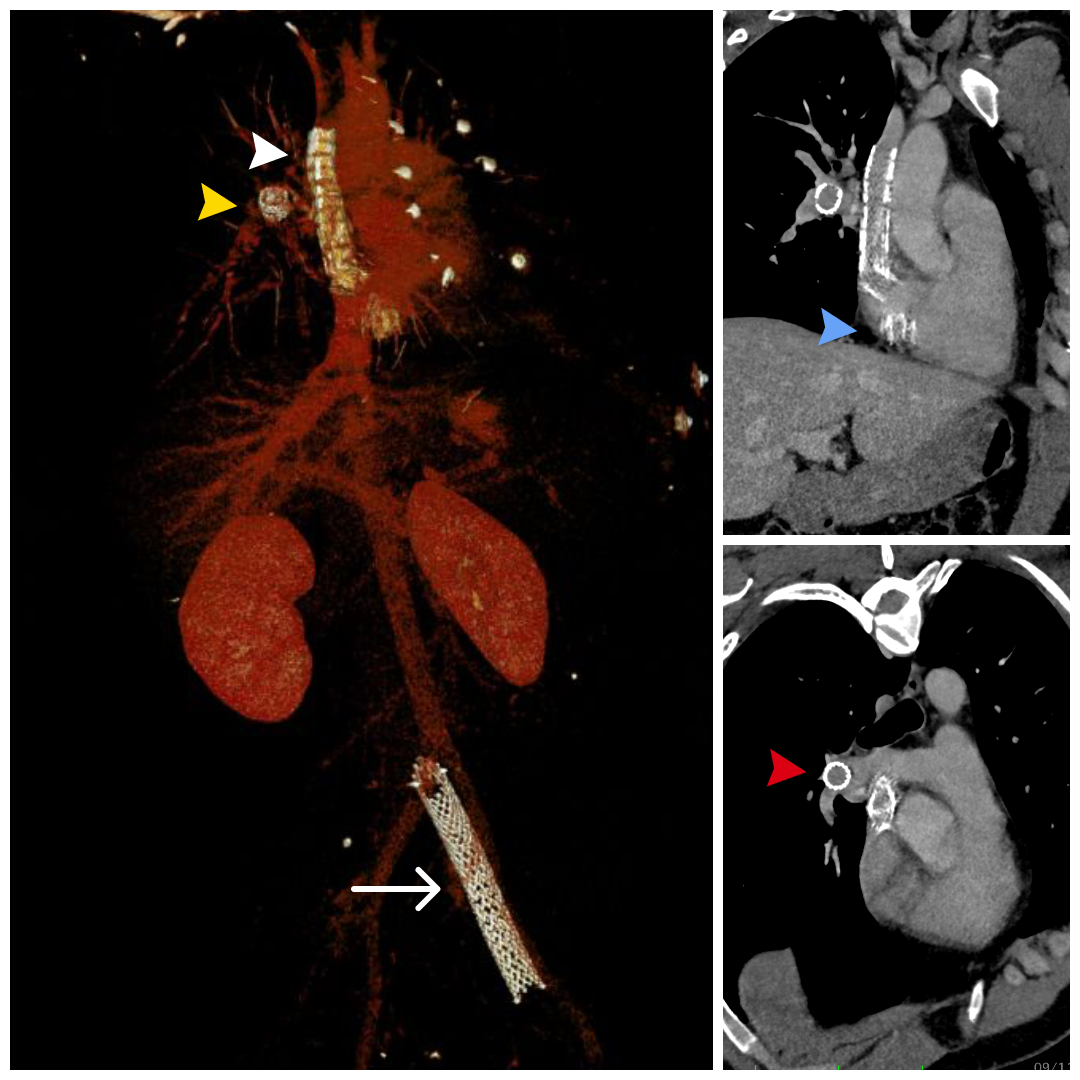

Image 2: Cardiac magnetic resonance. Left: tubular structure in the SVC with susceptibility artifact extending into the RA (white arrow). Right: single-shot LGE PSIR demonstrating contrast opacification within the stent lumen, consistent with preserved flow (yellow arrow). Image 3: Computed tomography. Left: 3D CTA reconstruction showing a stent in the left common iliac vein (white arrow), the embolized stent positioned within the RA with a fractured proximal edge and with its distal end lodged in the SVC (white arrowhead) and a small stent fragment located in the right pulmonary artery branch (yellow arrowhead). Upper right: View highlighting the relationship of the stent between the SVC and RA, with evidence of a fractured distal edge (blue arrowhead). Lower right: Axial view at the level of the pulmonary artery showing a metallic fragment in the right pulmonary artery branch (red arrowhead).

Image 3: Computed tomography. Left: 3D CTA reconstruction showing a stent in the left common iliac vein (white arrow), the embolized stent positioned within the RA with a fractured proximal edge and with its distal end lodged in the SVC (white arrowhead) and a small stent fragment located in the right pulmonary artery branch (yellow arrowhead). Upper right: View highlighting the relationship of the stent between the SVC and RA, with evidence of a fractured distal edge (blue arrowhead). Lower right: Axial view at the level of the pulmonary artery showing a metallic fragment in the right pulmonary artery branch (red arrowhead).